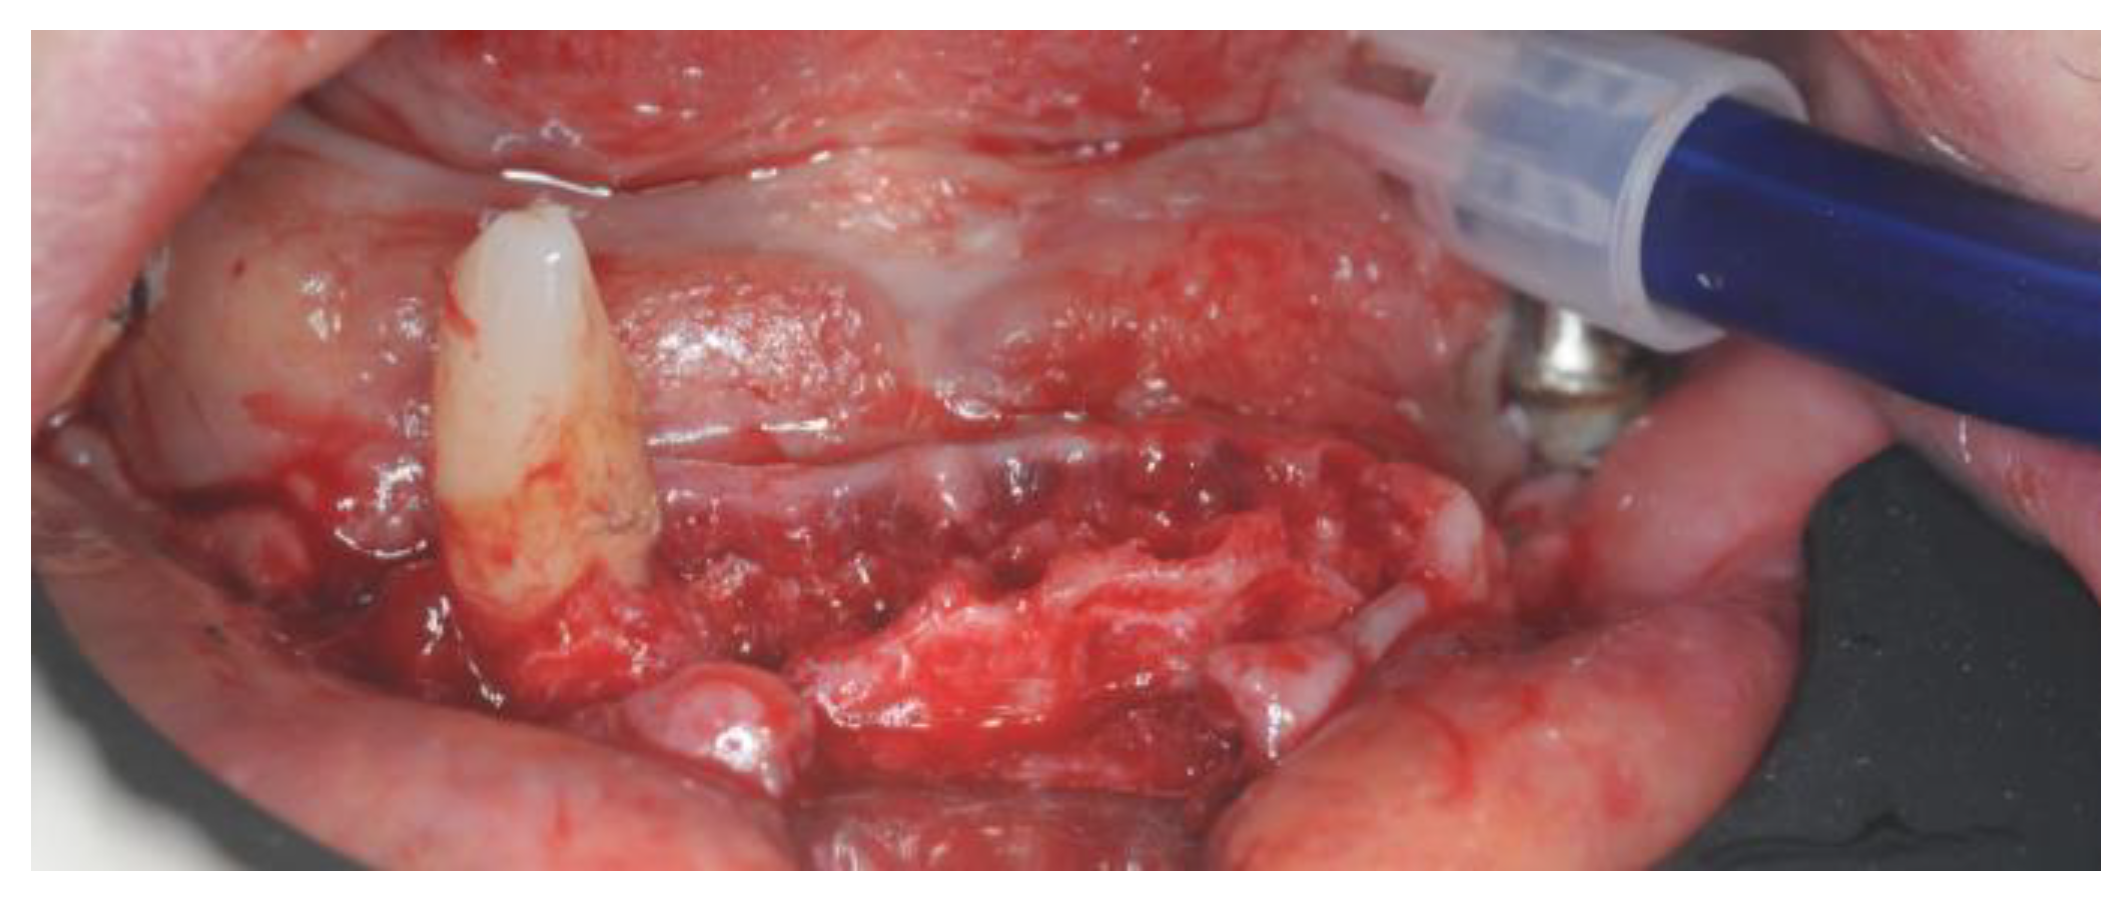

2.4. Surgery